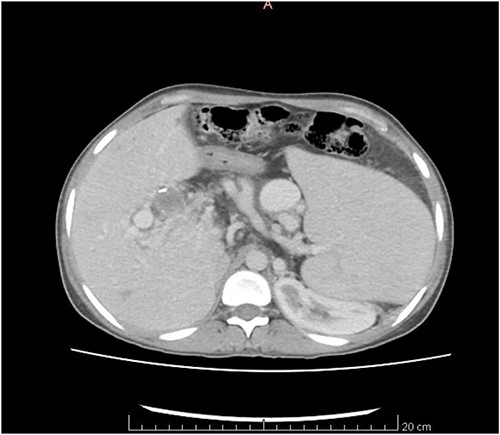

The CT scan exhibited features consistent with portal hypertension and associated changes in the pre-portal venous system, liver, and spleen (Figs 1 and 2).

CT scan coronal view showing gross hepatosplenomegaly with large collaterals suggestive of portal venous hypertension with portal biliopathy. Chronic thrombus seen in SMV and portal confluence.